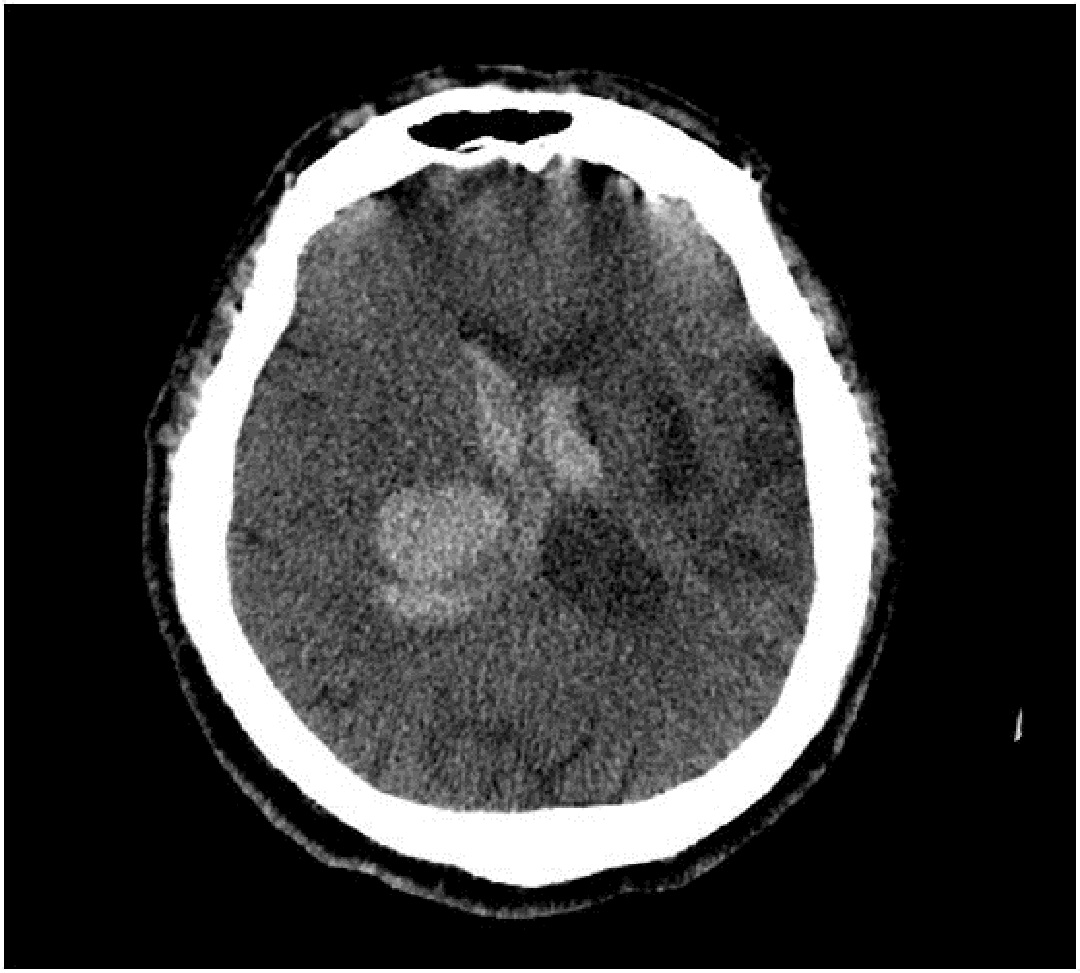

患者李xx,女,52歲,主因突發(fā)意識障礙伴左側(cè)肢體活動障礙1小時急診入院,查體:生命體征穩(wěn)定,昏迷狀態(tài),刺激略有睜眼,不發(fā)音,雙側(cè)瞳孔正大等圓,對光反射靈敏,刺痛肢體略屈曲,雙側(cè)巴氏征陽性,頭部CT平掃提示:右側(cè)基底節(jié)區(qū)腦出血。入院診斷:1.右側(cè)基底節(jié)區(qū)腦出血,2.高血壓3級,很高危。

術(shù)前CT